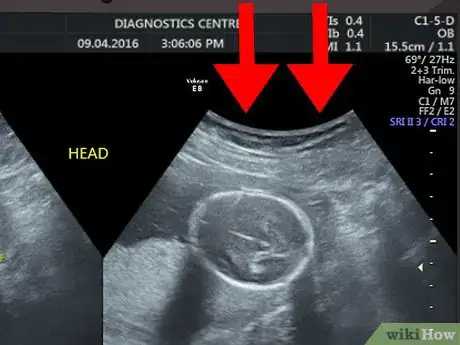

2Start from the top of the image. The top of the screen or printed image is where the ultrasound probe was placed. In other words, the image you see shows what the organ or tissues look like from the side rather than from the top.[2]

1Identify your womb. You can identify the outline of your uterus by finding the white or light grey line around the edges of the ultrasound image. Just inside of this area, there should be a black area. This is the amniotic fluid.[6] [7]

- Keep in mind that the edge of the womb may not go around the entire image. The technician may have positioned the probe in a way that centered the image on your baby. Even if you only see white or grey lines along one or two sides of the image, this is probably the outline of your womb.

2Spot the baby. Your baby will also look grey or whitish and will be located within the amniotic fluid (the dark area inside of the womb). Look at the area within your amniotic fluid to try to make out the outline and features of your baby.